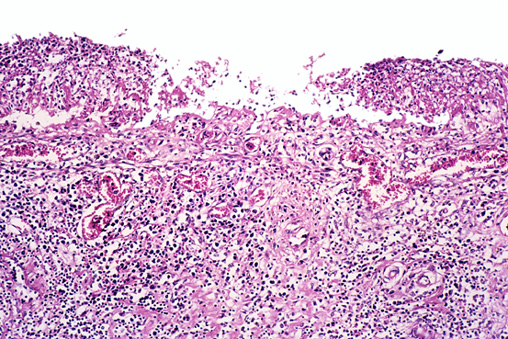

图片来自gettyimages